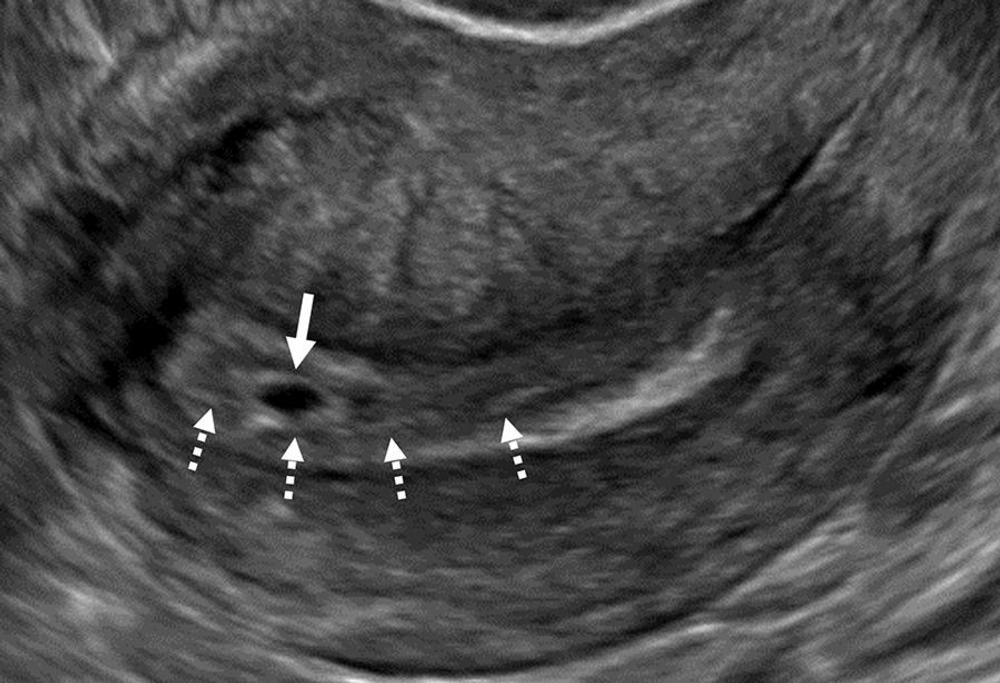

Figure 10. Interstitial ectopic pregnancy (EP). (A) Transvaginal transverse grayscale and (B) coronal reformatted three-dimensional US image in a 29-year-old pregnant patient shows a gestational sac (GS) (calipers) at 5 weeks 3 days. There is intervening myometrium (solid arrow) between the GS and endometrium (*). A claw sign (dotted arrows) of myometrial tissue confirms the pregnancy is implanted in the interstitial (intramyometrial) segment of the tube, termed an interstitial EP. The term ‘cornual EP’ should be avoided. Coronal reformatted three-dimensional US may better demonstrate an interstitial EP separate from the endometrium, as in this case. Diam = diameter.